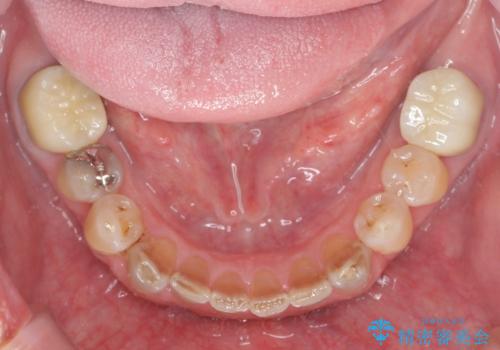

上顎は、残っている前歯も揺れがあり残すためにはクラウンでつなぐ歯周補綴が必要な状態です。

また咬合負担に不安のある前歯を助けるためにも、臼歯部にインプラント補綴を行いしっかりとかめる状態とすることも大切です。